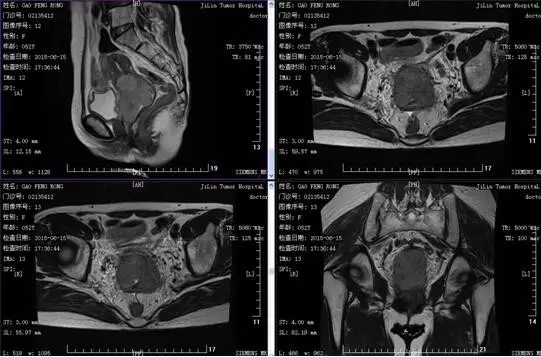

郜XX,女,52岁,因阴道不规则流血、异常分泌物、左腹痛2月,腰酸痛半个月于2015年6月15日入院。患者因阴道不规则流血2个月,增多伴异常分泌物、左下腹隐痛4天,腰部酸痛半个月,于某医院行彩超提示宫腔下段至宫颈不均略低回声。宫颈病理活检:(宫颈组织)浸润性鳞状细胞癌Ⅱ级。为行进一步治疗入我科。病程中食睡可,二便如常,近1月体重减轻约4kg。妇科检查:外阴发育正常,已婚已产型,阴道尚通畅,粘膜光滑,阴道前壁僵硬见不规则隆起,质硬,达阴道下1/3,前穹窿消失,宫颈失去正常形态,表面呈溃疡型,宫颈增桶状增粗,约5×6cm,子宫大小形态正常,活动度尚可,双附件未触及。双侧宫旁短缩,弹性欠佳,未达盆壁。肛门无异常,直肠粘膜光滑,指套未染血。宫颈病理活检(某医院,2015-06-11):(宫颈组织)浸润性鳞状细胞癌Ⅱ级。临床诊断:宫颈鳞癌ⅢA期。盆腔MRI检查:宫颈增大,壁增厚,见不规则软组织肿块影,肿块向下累及阴道,侵犯至阴道下1/3段,部分病灶累及宫颈外膜,周围脂肪间隙见索条影,病变长径约为6.5cm,膀胱后壁局部受压,脂肪间隙模糊。盆腔内见多个略大淋巴结,较大约为1.0×1.0cm。1.宫颈癌伴宫旁侵润(IIIA期可能性大),不除外侵犯膀胱后壁。2.盆腔淋巴结略增大,不除外转移。